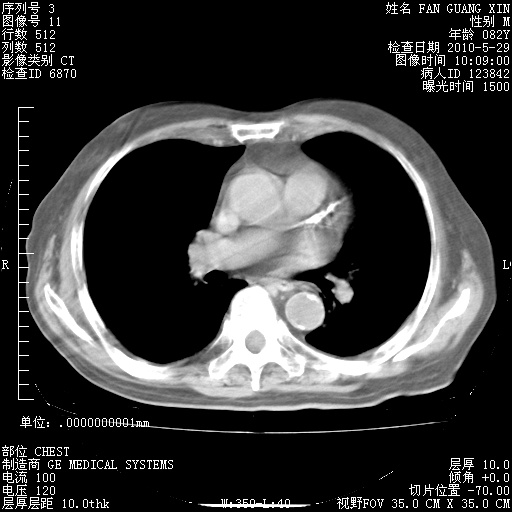

再治疗10天后的肺部CT

再治疗10天后的肺部CT 纵膈窗

阅读此次胸部CT,肺间质渗出性改变较入院时有吸收。目前从体温、白细胞、中性分叶明显增高,肯定存在细菌感染(发生医院感染哦,若无消化道及泌尿系统等感染的依据,肺部感染可能大)。若你院头孢哌酮舒巴坦钠耐药率较高,同意你的方案,若48小时体温仍高,可考虑使用碳青霉稀类抗菌药物,同时可予超声雾化、注意滴数时加大液体量。白蛋白33.30g/L较低哦,需加强营养等支持治疗。